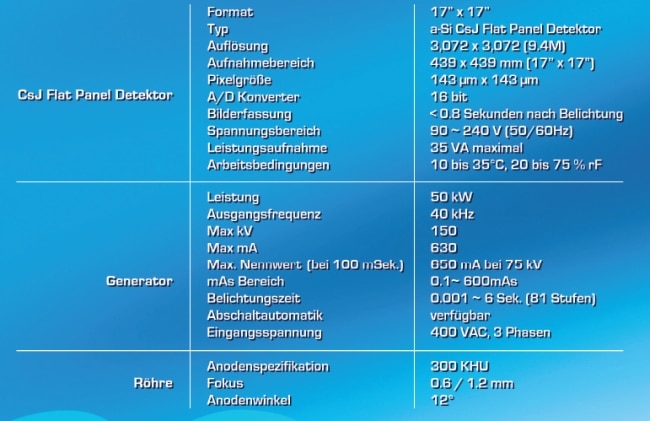

- Beste Bildauflösung durch den CsJ Flat Panel Detektor

- Konstante Strahlenqualität des HF-Generators und der Dreh-Anoden-Röhre

- Eingebauter CsJ-Detektor und EcoView Bildverarbeitungs-Software für qualitativ hochwertige Bilder

Die Kombination aus dem Detektor mit seinem hocheffizienten Cäsiumiodid (CsI) Scintillator und einer digitalen Bildverarbeitung ermöglicht niedrigere Strahlendosen. Die Bilder sind selbst bei niederdosierten Anwendungen von bester Qualität.